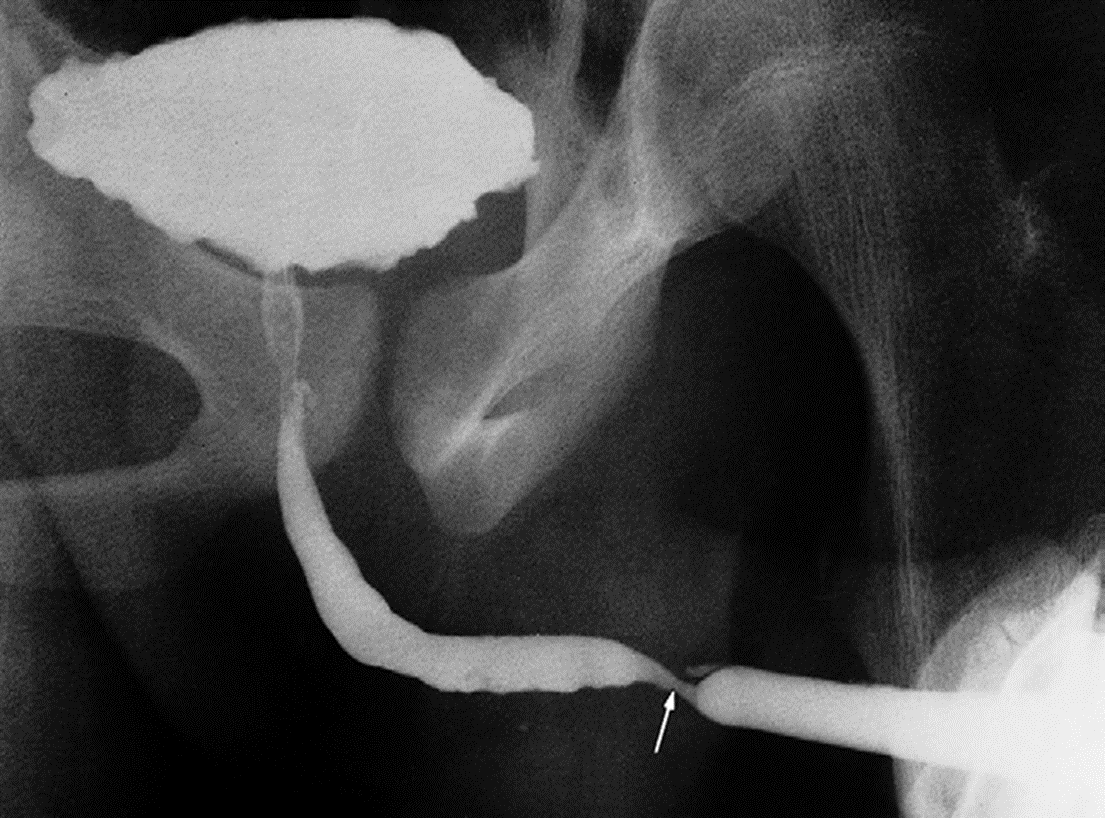

Urethral stricture. An ascending urethrogram showing a stricture in the penile urethra (arrow). The patient had gonorrhoea.